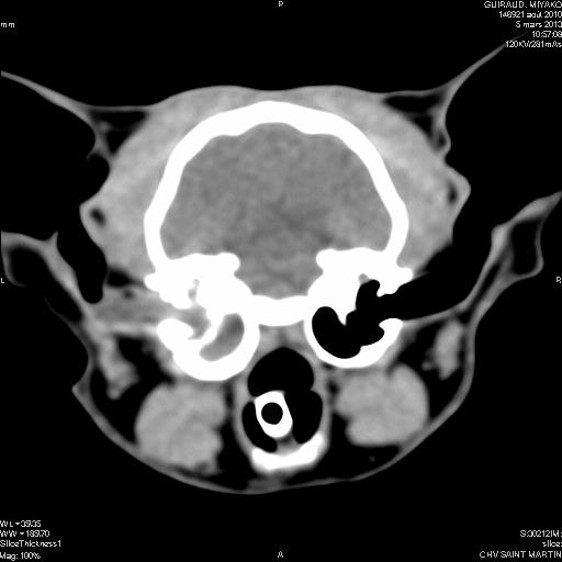

-Les maladies de l'oreille du chien et du chat : pathogénie et clinique différentielles. Indications chirurgicales.

-Indications et contre-indications, descriptions et résultats des techniques conservatrices et chirurgicales de l'oreille chez le chat.